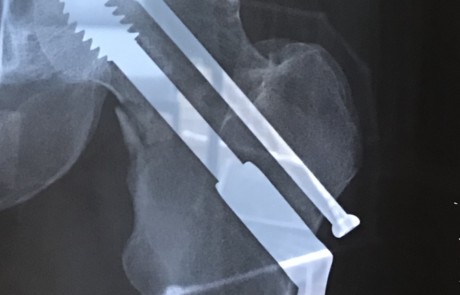

I was hit by an SUV on March 24, 2018, towards the end of a 6.5 hour training ride with a friend. The crash resulted in several injuries including a badly broken left hip. I was operated on several hours later and put back together admirably by a great surgeon with some impressive titanium bolts, rod & screws! (Thank God for modern western medicine, I say.) The surgeons told me that I was to be 50% weight bearing on the injured leg immediately, so the very next morning they turned up at my hospital bed with a walking frame and insisted I get up. Quite amazing really, and so rehab started within 24 hours of the accident.